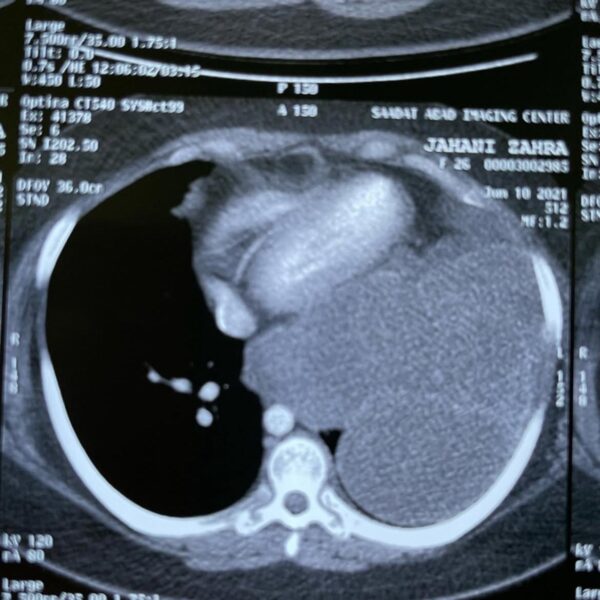

توضیح: جراحی بیمار با فیستول بین نای و مری